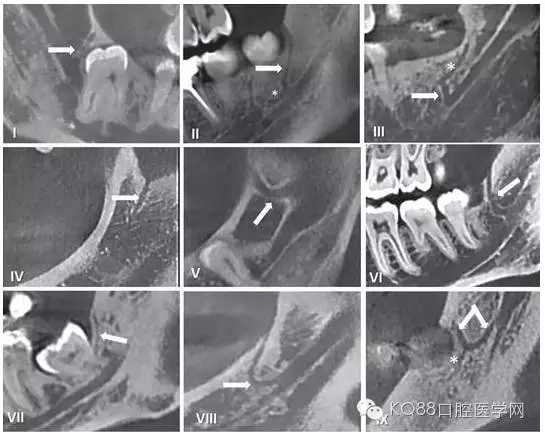

在臨床工作中,個體解剖差異導致像磨牙后管這類的神經(jīng)分叉及神經(jīng)走行的變化,術前只能通過放射方法檢測。但使用口腔曲面斷層片之類的常規(guī)二維影像學照片是難以檢查到的。隨著現(xiàn)代醫(yī)學影像技術的發(fā)展,出現(xiàn)了計算機斷層掃描(CT)和錐束CT(CBCT),其在口腔醫(yī)學領域的成功運用使得磨牙后管的術前影像評估成為可能。精確的捕捉到下頜磨牙后管的解剖走行,需要高分辨率的成像設備并保證攝像期間患者沒有晃動。下面我們將用幾張CBCT影像圖片為大家圖示說明。

圖五 使用CBCT拍攝到的不同走行的下頜后管